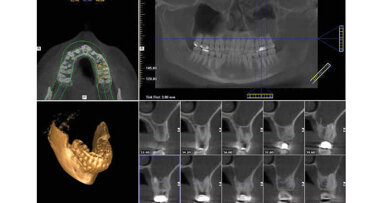

Le sinus maxillaire est le plus grand sinus paranasal et sa partie inferieure est délimitée par le processus alvéolaire.1 La relation topographique ...